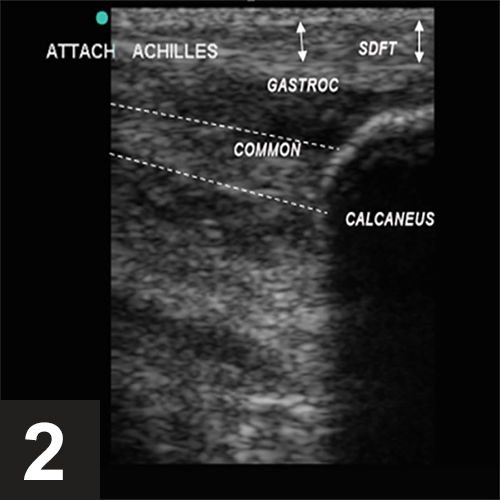

from www.cliniciansbrief.com

Top 5 Muscle & Tendon Injuries in Lame Patients Clinician's Brief